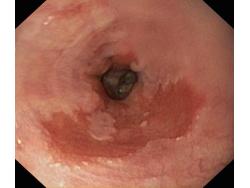

Przełyk Barretta